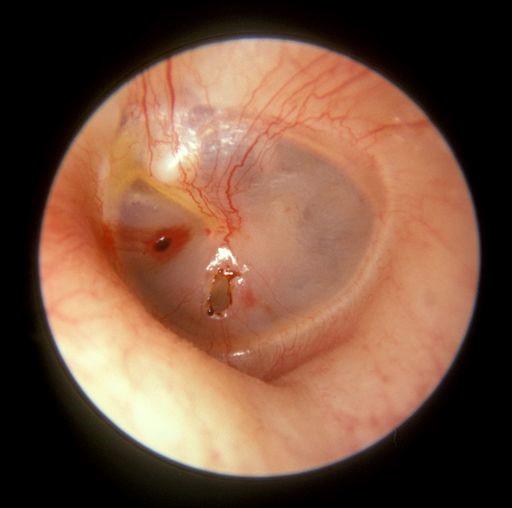

Perforation of the tympanic membrane

© Michael Hawke MD (Own work), CC BY 4.0, via Wikimedia Commons

Chronic suppurative otitis media (CSOM) is a chronic inflammation of the middle ear and mastoid cavity. It is predominantly a disease of the developing world. Clinical features are recurrent otorrhoea through a tympanic perforation, with conductive hearing loss of varying severity.

The tympanic membrane is perforated in CSOM. If this is a tubotympanic perforation (in the centre of the tympanic membrane), it is usually 'safe', whilst atticoantral perforation (at the top of the tympanic membrane) is often 'unsafe'. Safe or unsafe depends on the presence of cholesteatoma: